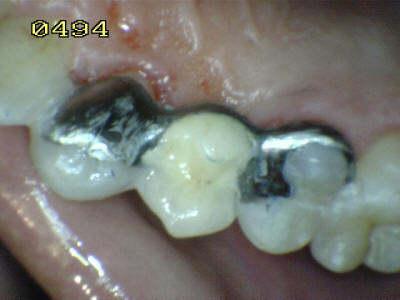

El material oscuro es una

amalgama cubierta por el diseño del puuente; observe los restos

de cemento adherido al esmalte dental.

Caries de esmalte y dentina

en el otro pilar (flechas rojas)